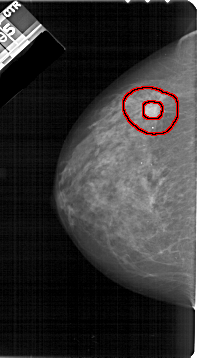

A_1211_1.LEFT_CC

LEFT_CC LINES 5356 PIXELS_PER_LINE 2971 BITS_PER_PIXEL 12 RESOLUTION 43.5 OVERLAY

FILE: A_1211_1.LEFT_CC.OVERLAY

TOTAL_ABNORMALITIES 1

ABNORMALITY 1

LESION_TYPE MASS SHAPE IRREGULAR MARGINS SPICULATED

ASSESSMENT 5

SUBTLETY 5

PATHOLOGY MALIGNANT

TOTAL_OUTLINES 2

BOUNDARY

CORE